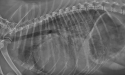

Rechtsseitiges Thoraxröntgenbild eines kleinen Hundes im ACVIM Stadium C, Herzinsuffizienz.

Bild mit freundlicher Genehmigung von Rebecca L. Stepien, DVM, MS, DACVIM (Kardiologie), Universität von Wisconsin, USA